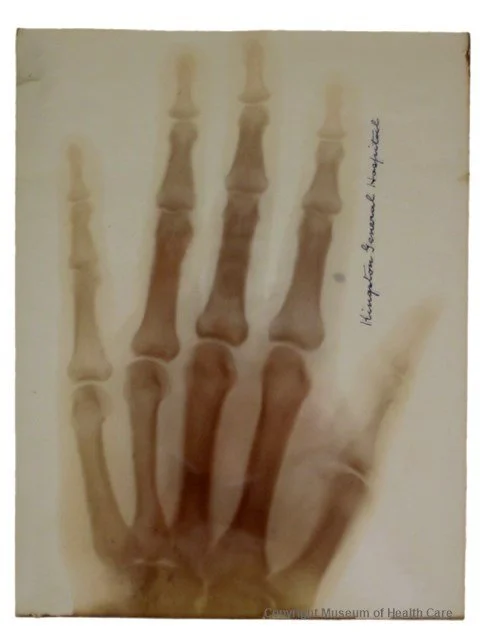

Röntgen is most famous, however, for his discovery of x-rays in 1895. While experimenting with cathode rays and vacuum tubes, he discovered a new kind of ray which could pass through different types of materials, but was stopped by others. He continued to experiment with these strange rays, which he dubbed “x-rays” because “x” indicated an unknown variable in mathematics. He soon took the first medical x-ray of his wife Anna’s hand, revealing her bones and capturing as well the ring she wore on her finger. Upon seeing this, she famously exclaimed “I have seen my death!”

Many of Röntgen’s colleagues insisted on calling the sensational new rays “Röntgen Rays,” after their discoverer, but Röntgen protested. His own moniker for the discovery had stuck in English, but in many languages they remain named after him. X-rays made a massive splash in many areas of the scientific world very quickly, leading to over 1000 articles being published on the subject in 1896 alone, and Röntgen being awarded the first Nobel Prize in Physics in 1901.